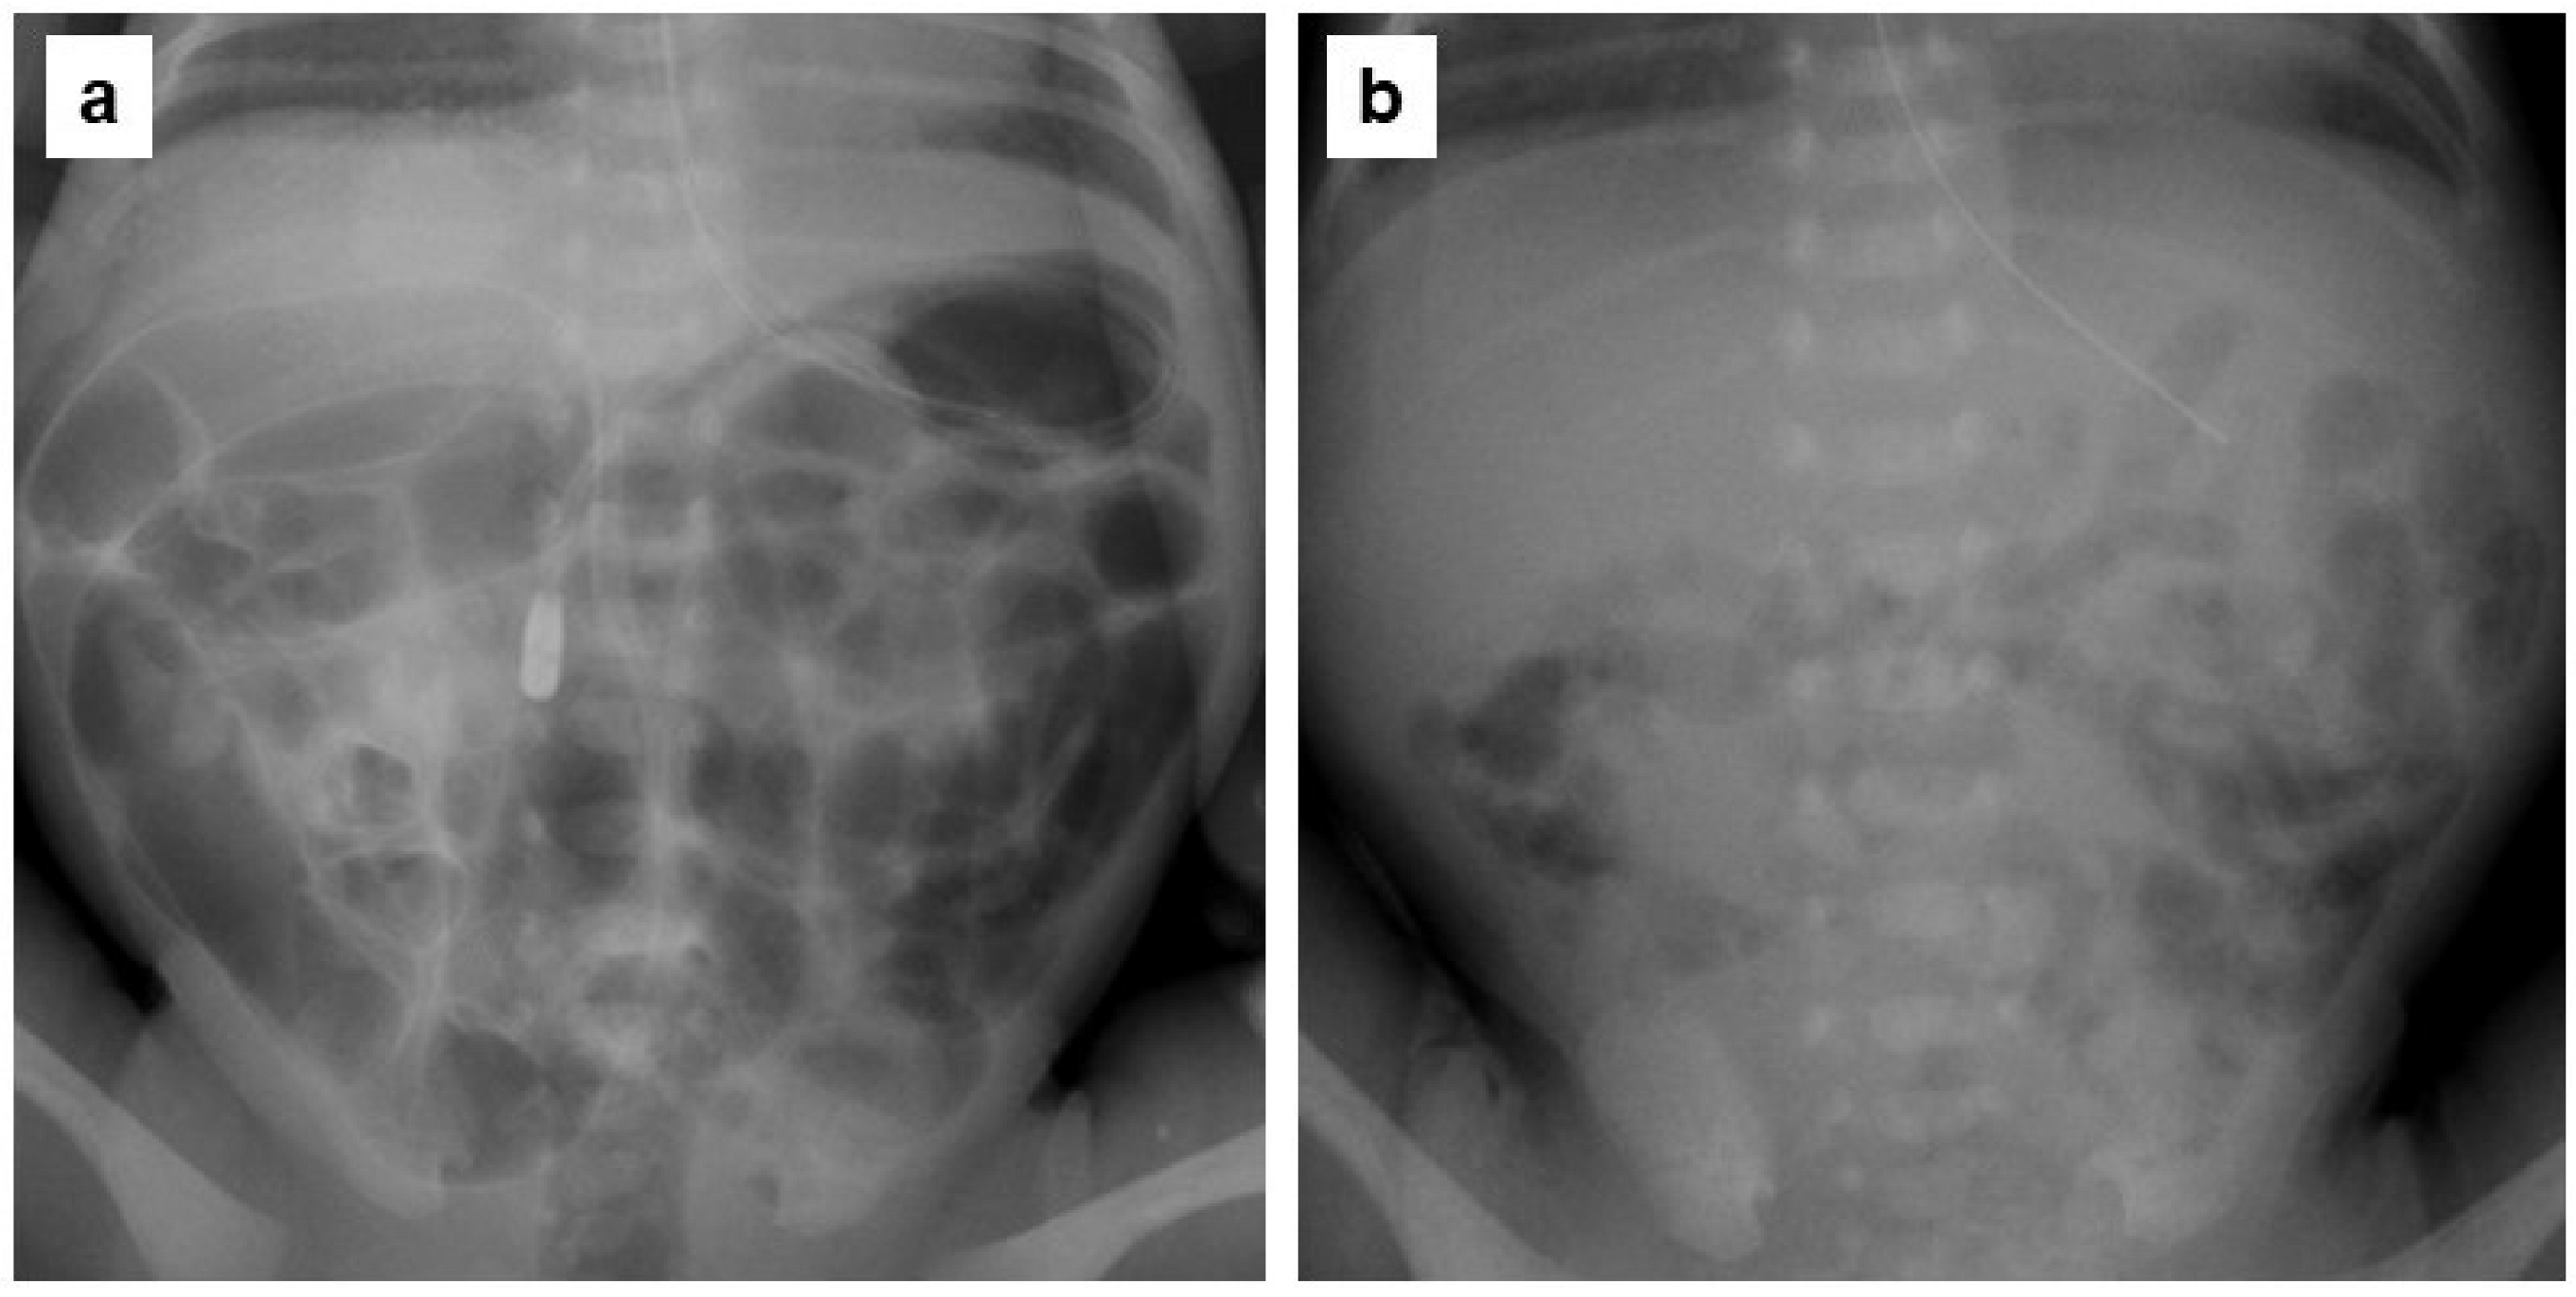

2.5. Evaluation of Abdominal Gas Areas

- Koide, A.; Yamaguchi, T.; Odaka, T.; Koyama, H.; Tsuyuguchi, T.; Kitahara, H.; Ohto, M.; Saisho, H. Quantitative analysis of bowel gas using plain abdominal radiograph in patients with irritable bowel syndrome. Am. J. Gastroenterol. 2000, 95, 1735–1741. [Google Scholar] [CrossRef]